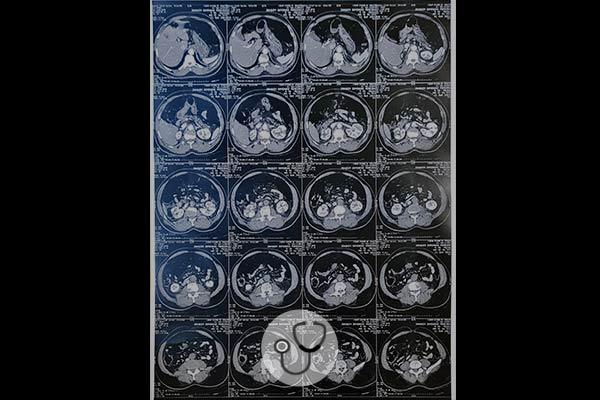

Através de um aparelho de ultrassom portátil, foram feitas as seguintes imagens do coração da paciente: